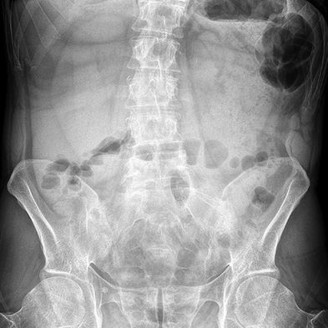

Practice Orthopedics online MCQs and assess your clinical knowledge. High-yield questions for medical students and orthopedic residents.